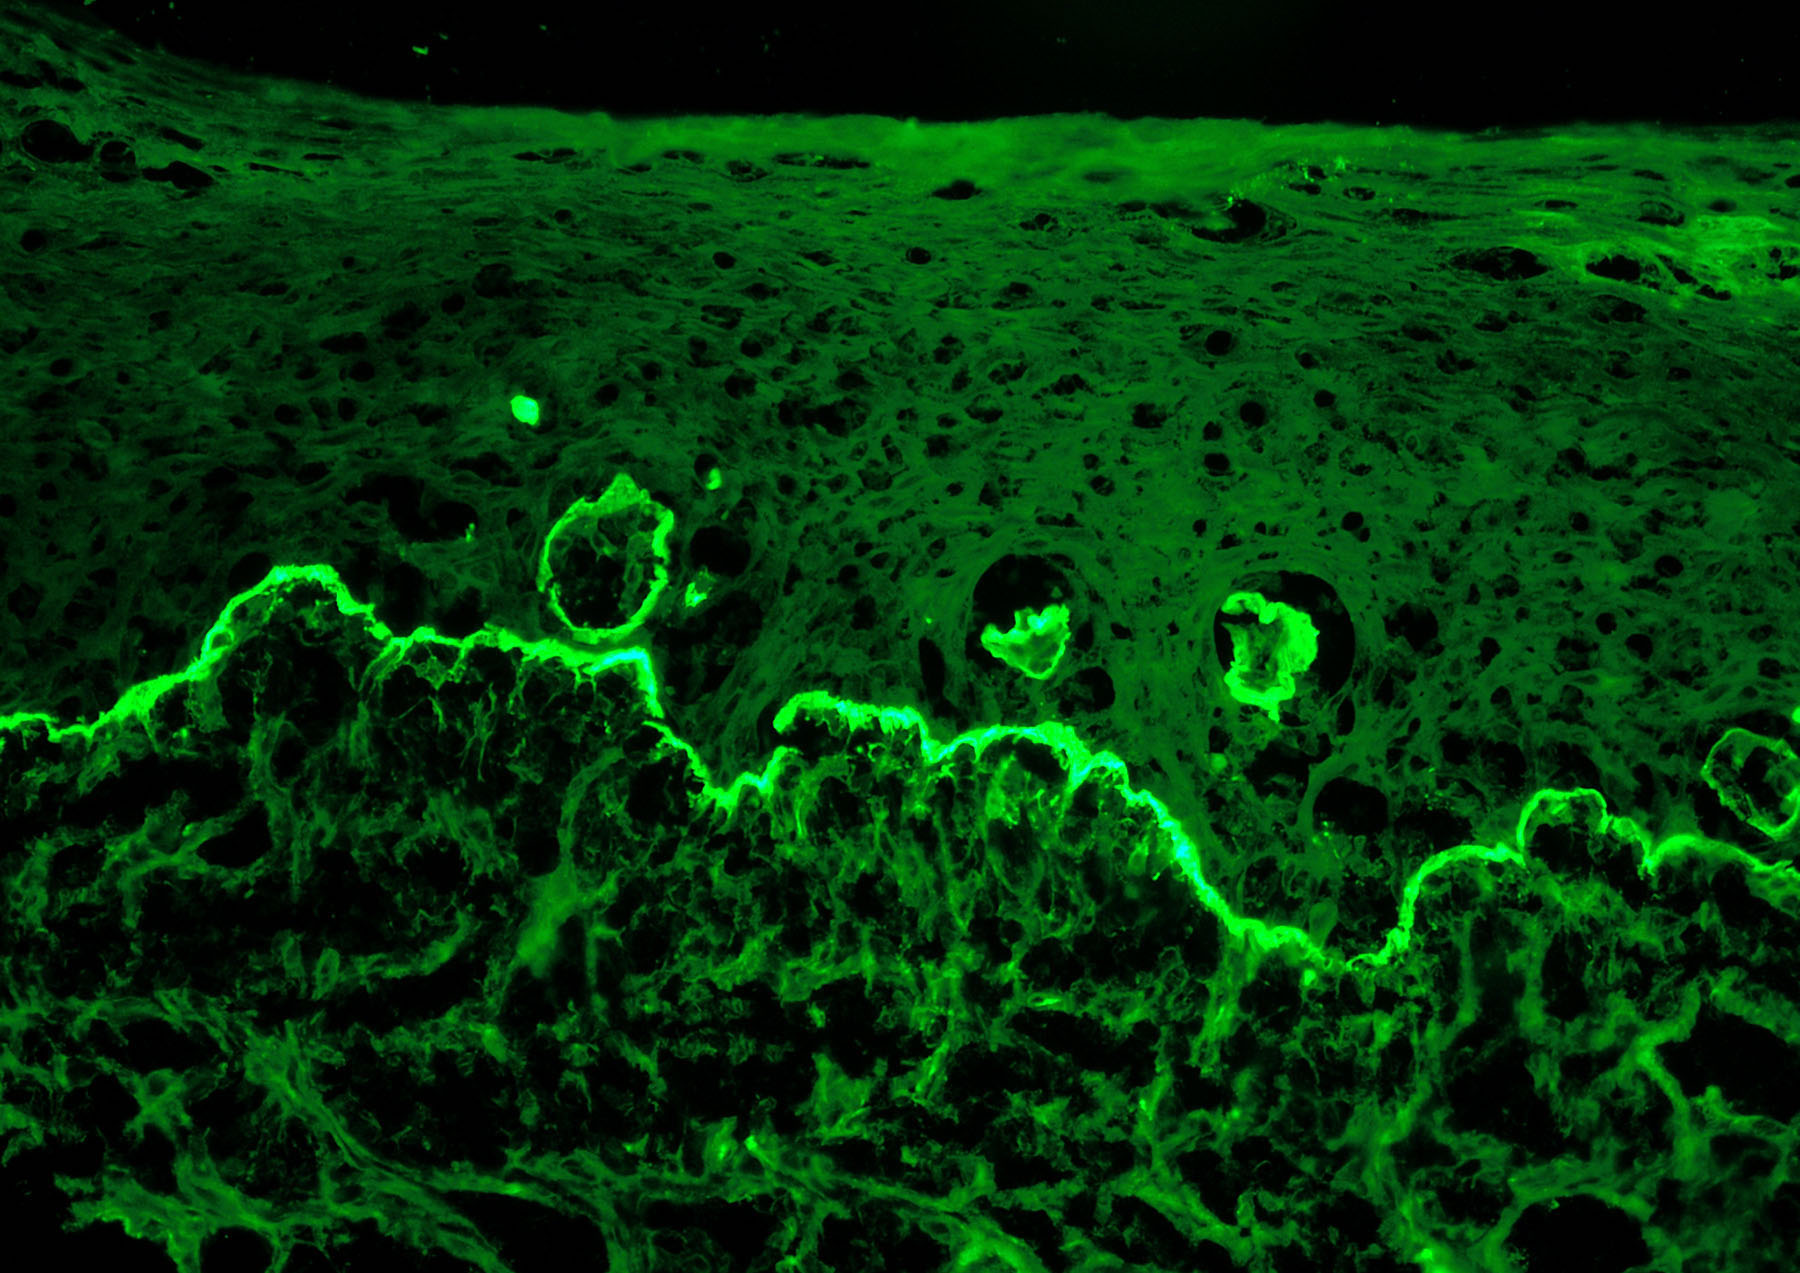

Η ιστοπαθολογική εικόνα του ομαλού λειχήνα είναι τυπική

Δείχνει διήθηση της επιδερμίδας από λεμφοκύτταρα που βρίσκονται, ακριβώς, κάτω από την επιδερμίδα και έχουν την διάταξη ζώνης. Χαρακτηριστικά είναι τα κολλοειδή σωμάτια που χρωματίζονται ερυθρά με χρώση ηωσίνης.